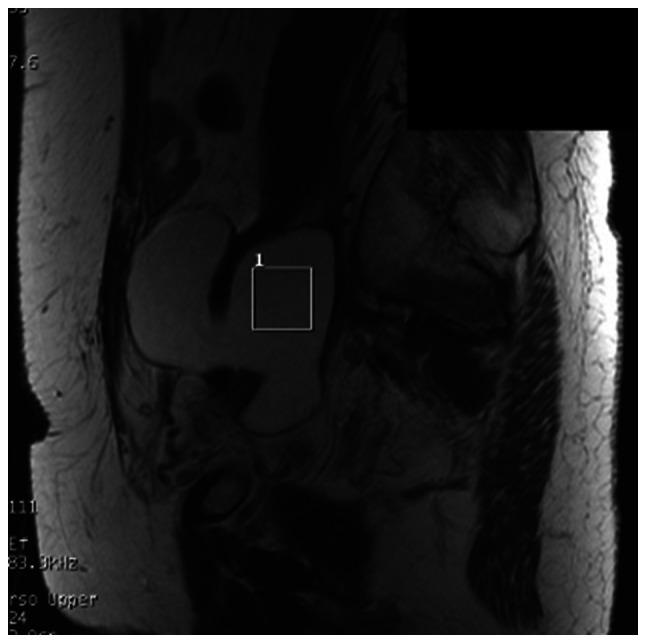

Due to the invasiveness of sample collection, treatment for an abscess in the pelvis, such as a gynecological abscess, is often started without a culture test. A test that could predict the appropriate antibiotic and clinical course without invasiveness prior to treatment initiation would be useful. Magnetic resonance spectroscopy (MRS) can be used to detect metabolites in an abscess and has the potential for evaluation of gynecological abscesses. The present study investigated the use of MRS for the evaluation of gynecological abscesses, using next-generation sequencing (NGS) for detection of true pathogenic bacteria. A total of 16 patients with a gynecological abscess who were treated at Keio University Hospital (Tokyo, Japan) from July 2015 to September 2016 and underwent MRS were recruited to the present study. If available, samples from drainage or surgery were used for detection of true pathogenic bacteria based on analyses of bacterial flora using NGS of 16S ribosomal DNA. MRS signals, NGS results and clinical course were then compared. All patients gave written informed consent after receiving an oral explanation of the study and the study was approved by the institutional research ethics committee. Of the 16 patients, six had MRS signals with a specific peak at 1.33 ppm, which suggested the presence of lipid or lactic acid. However, there was no significant association between metabolism, MRS signals, pathogenesis and clinical course. Only in cases of infectious lymphocele were there cases with a lactic acid peak that seemed to improve without drainage. In conclusion, the present study was not able to show marked usefulness of MRS for the identification of pathogenic bacteria and prediction of the clinical course; however, MRS may be useful for predicting the need for drainage in patients with infectious lymphocele. This study was registered as a clinical trial in the UMIN Clinical Trials Registry (registration no. UMIN000016705) on March 11, 2015.

由于样本采集具有侵入性,盆腔脓肿(如妇科脓肿)的治疗通常在未进行培养检测的情况下就开始了。一种能够在治疗开始前非侵入性地预测合适抗生素和临床病程的检测方法将很有用。磁共振波谱(MRS)可用于检测脓肿中的代谢物,具有评估妇科脓肿的潜力。本研究使用下一代测序(NGS)检测真正的致病细菌,探讨了MRS在评估妇科脓肿中的应用。2015年7月至2016年9月在庆应义塾大学医院(日本东京)接受治疗并接受MRS检查的16例妇科脓肿患者被纳入本研究。如果有引流或手术样本,基于对16S核糖体DNA的NGS分析细菌菌群,用于检测真正的致病细菌。然后比较MRS信号、NGS结果和临床病程。所有患者在接受研究的口头解释后均签署了书面知情同意书,该研究获得了机构研究伦理委员会的批准。16例患者中,6例MRS信号在1.33 ppm处有特定峰,提示存在脂质或乳酸。然而,代谢、MRS信号、发病机制和临床病程之间没有显著关联。仅在感染性淋巴囊肿病例中,有乳酸峰的病例似乎在未引流的情况下有所改善。总之,本研究未能显示MRS在鉴定致病细菌和预测临床病程方面有显著作用;然而,MRS可能有助于预测感染性淋巴囊肿患者是否需要引流。本研究于2015年3月11日在UMIN临床试验注册中心注册为临床试验(注册号UMIN000016705)。